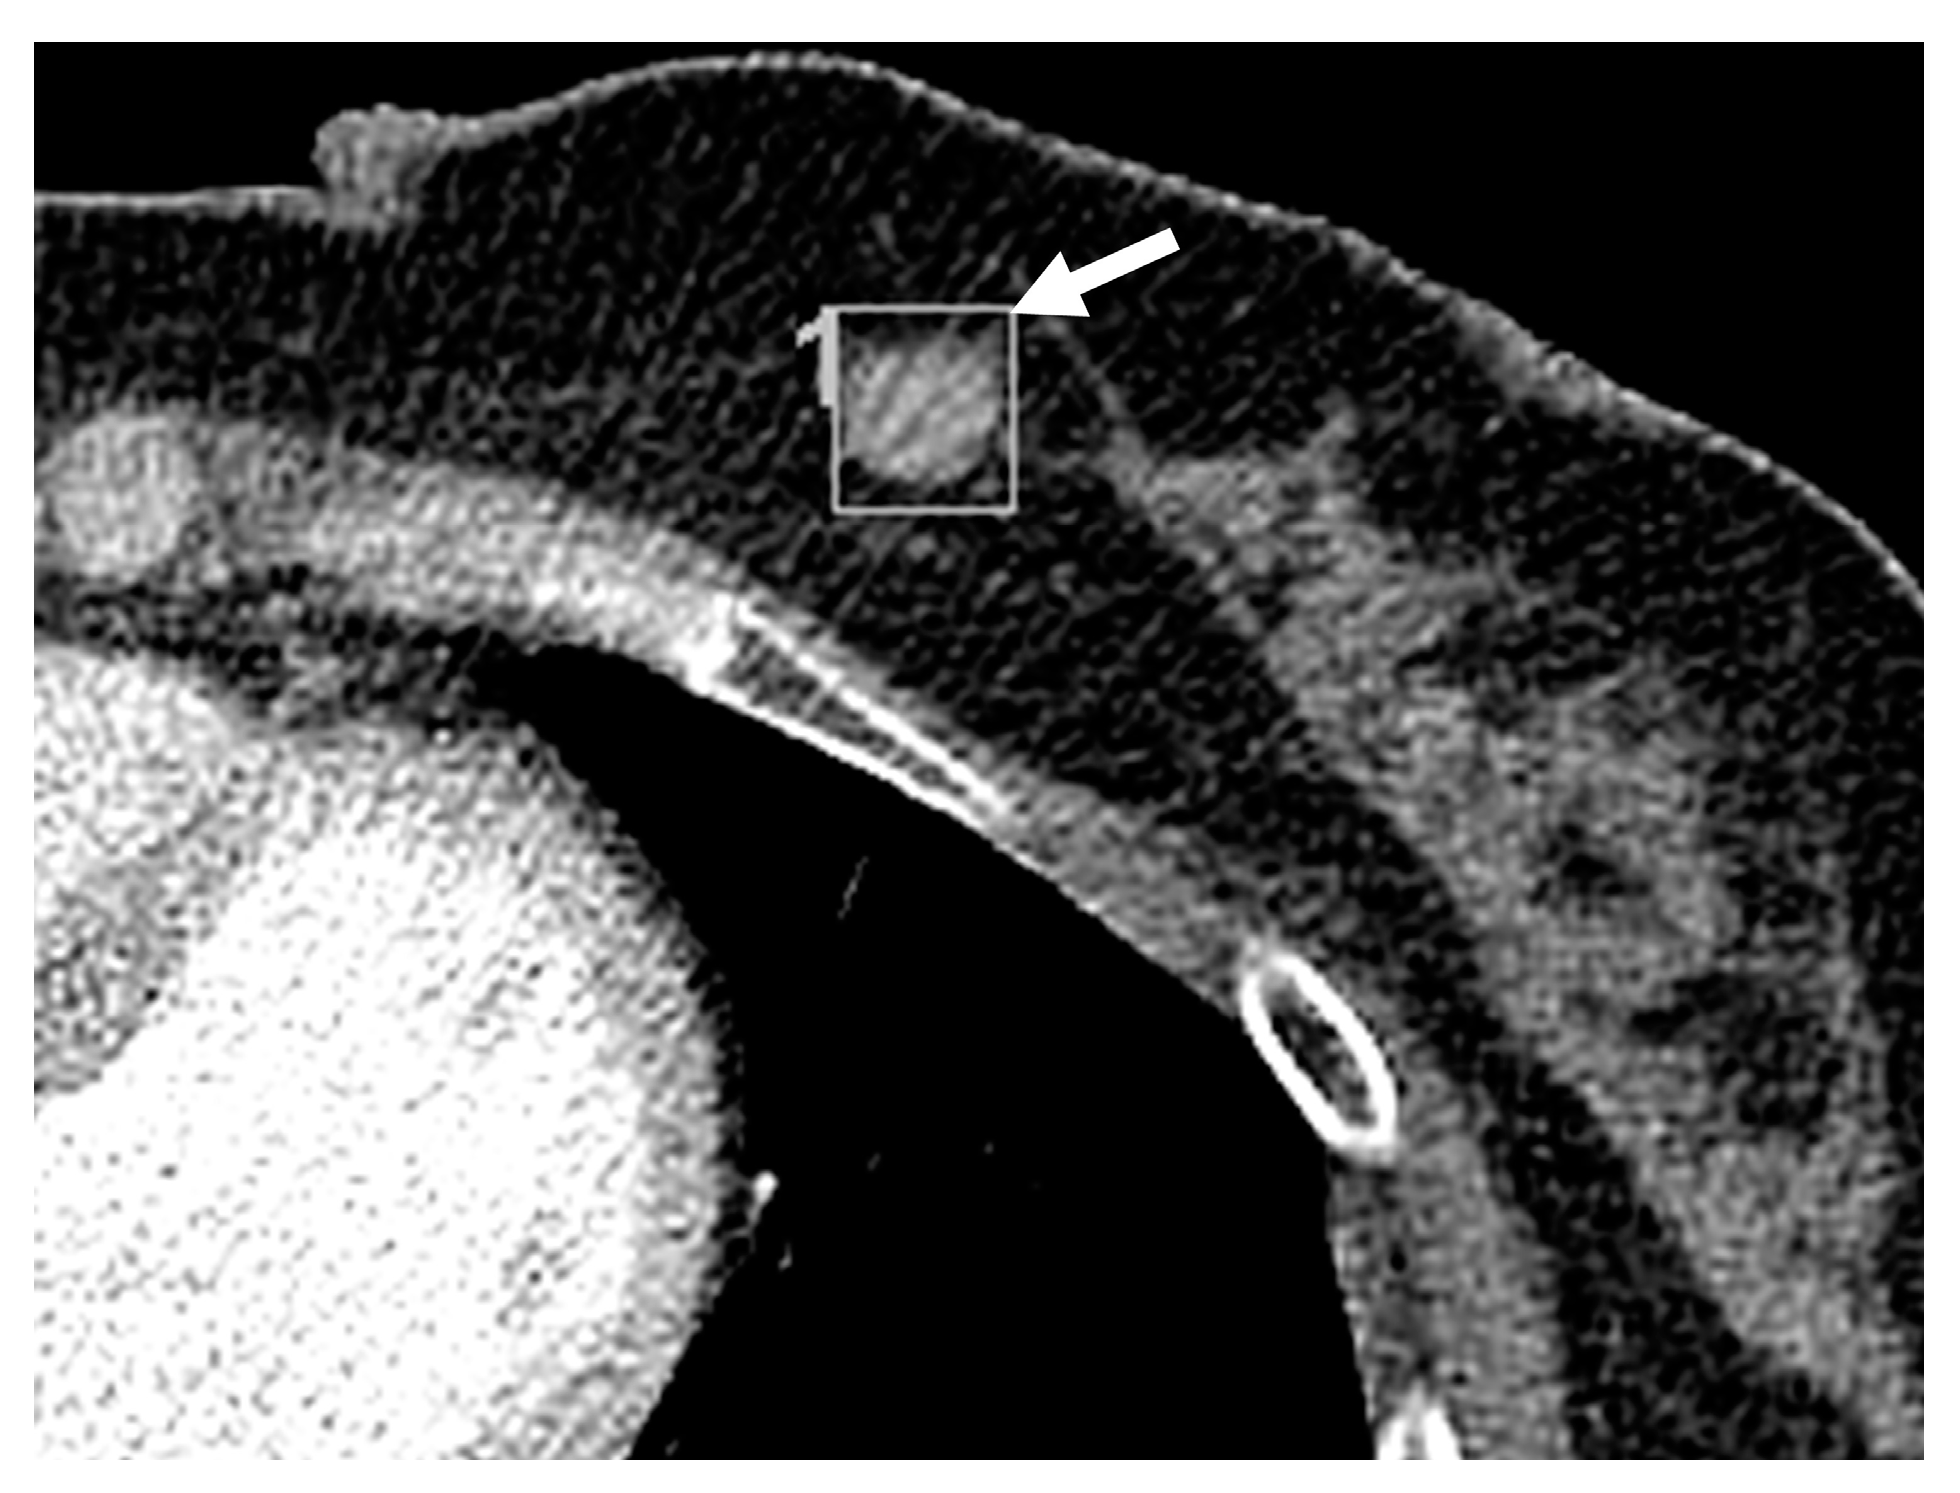

Missed and Detected Incidental Breast Cancers on Contrast Enhanced Chest CT: Detection Rates and CT Features

3.2. Imaging Features of Missed and Detected Breast Cancers

3.3. Imaging Features Associated with Missed Breast Lesions Group